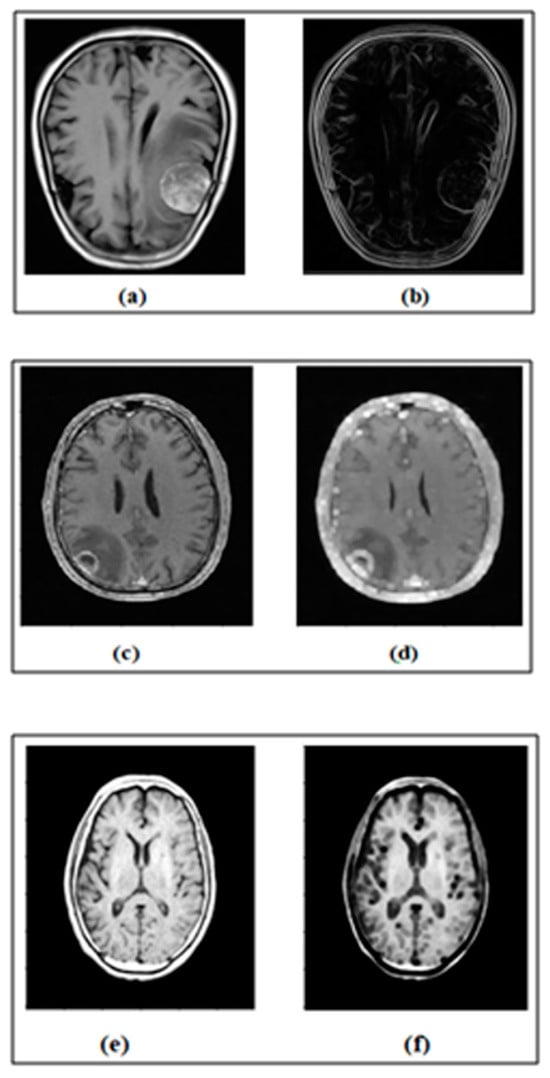

The properties of edge detection and morphological operations are used as MRs. In IP, edge detection plays a vital role in identifying the immediate changes in grayscale images. Identifying the edges of the images can be invaluable for different real-world applications [26]. Similarly, dilation and erosion are the main morphological operations that increase or decrease the region of the image according to the structuring element [2]. The inputs and outputs of the edge detection program, a dilation and erosion program, are given in Figure 3.

Figure 3 shows the sample inputs of MRI brain images and their expected output images after performing edge detection, dilation operation and erosion operation.

Figure 3. (a) Input image. (b) Output of edge detection. (c) Input image. (d) Output of dilation. (e) Input image. (f) Output of erosion.